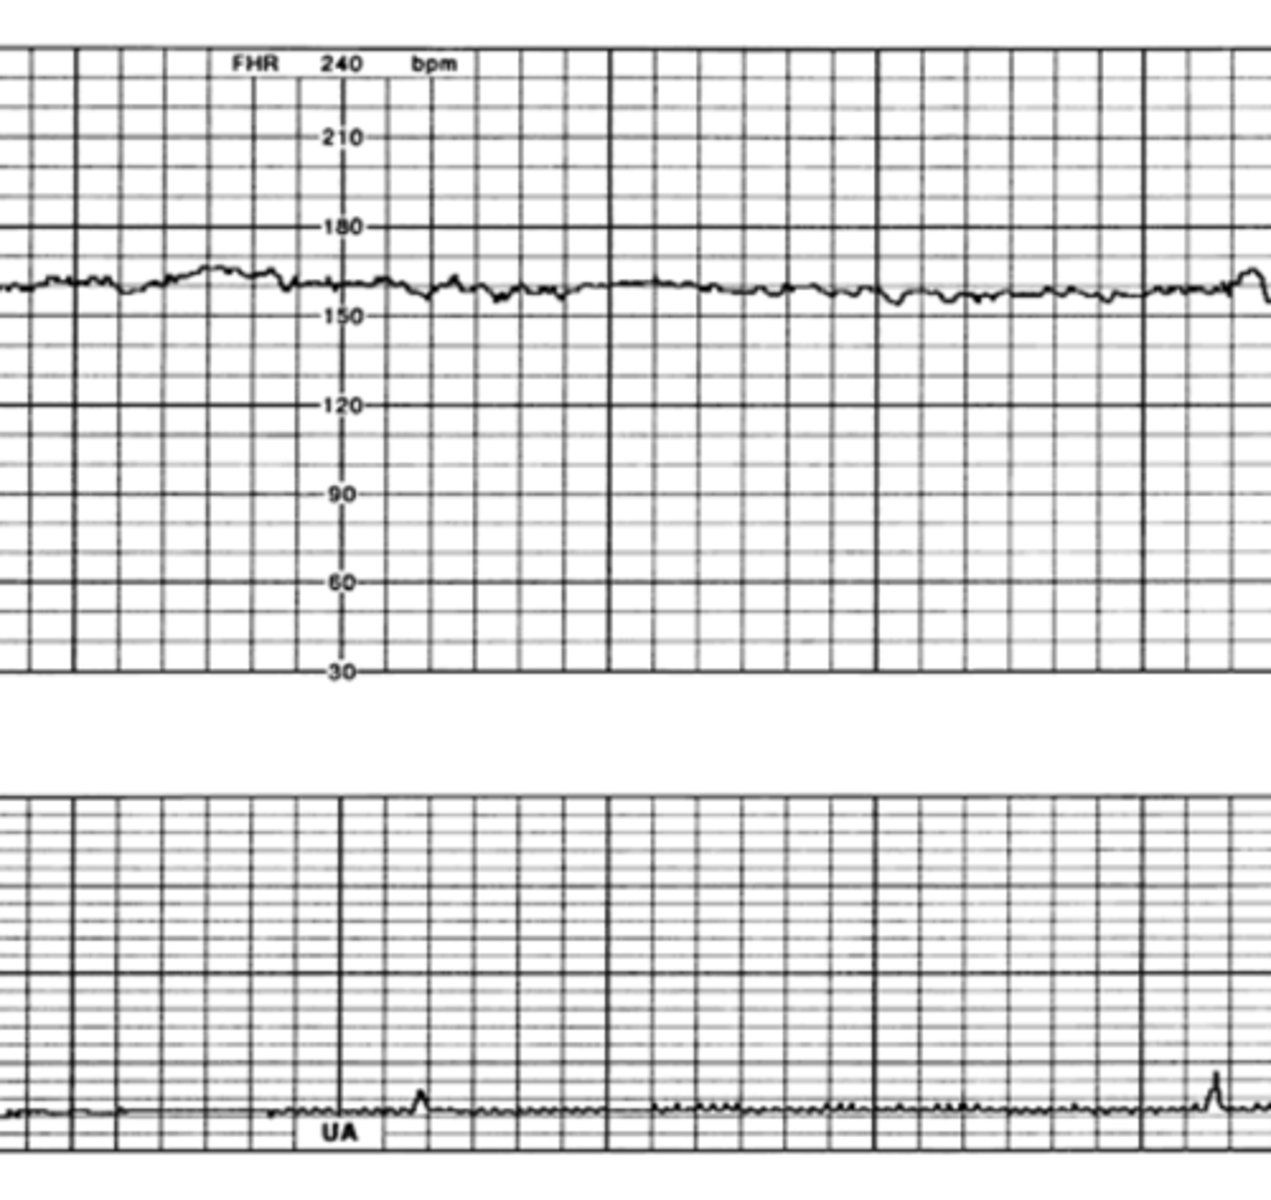

Absent

How would you classify this variability?

Minimal